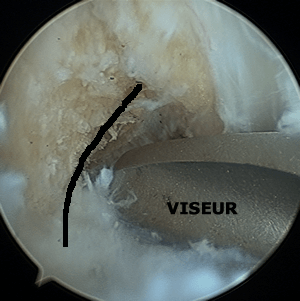

La technique SAMBA

La photo ci-dessous, montre une vue sous arthroscopie de la greffe à la fin de l'intervention. Elle sort du tunnel tibial dans les restes du l'ex ligament croisé antérieur (technique appelée SAMBA).

Le but de cette technique (que tous les chirurgiens utilisent a priori) est de préserver tous les tissus restants, car ils sont d'une part, remplis de "mécano-récepteurs" utiles pour la proprioceptivité, et d'autre part, ces tissus vascularisés en enveloppant la greffe, vont participer à la revascularisation ultérieure de la greffe.